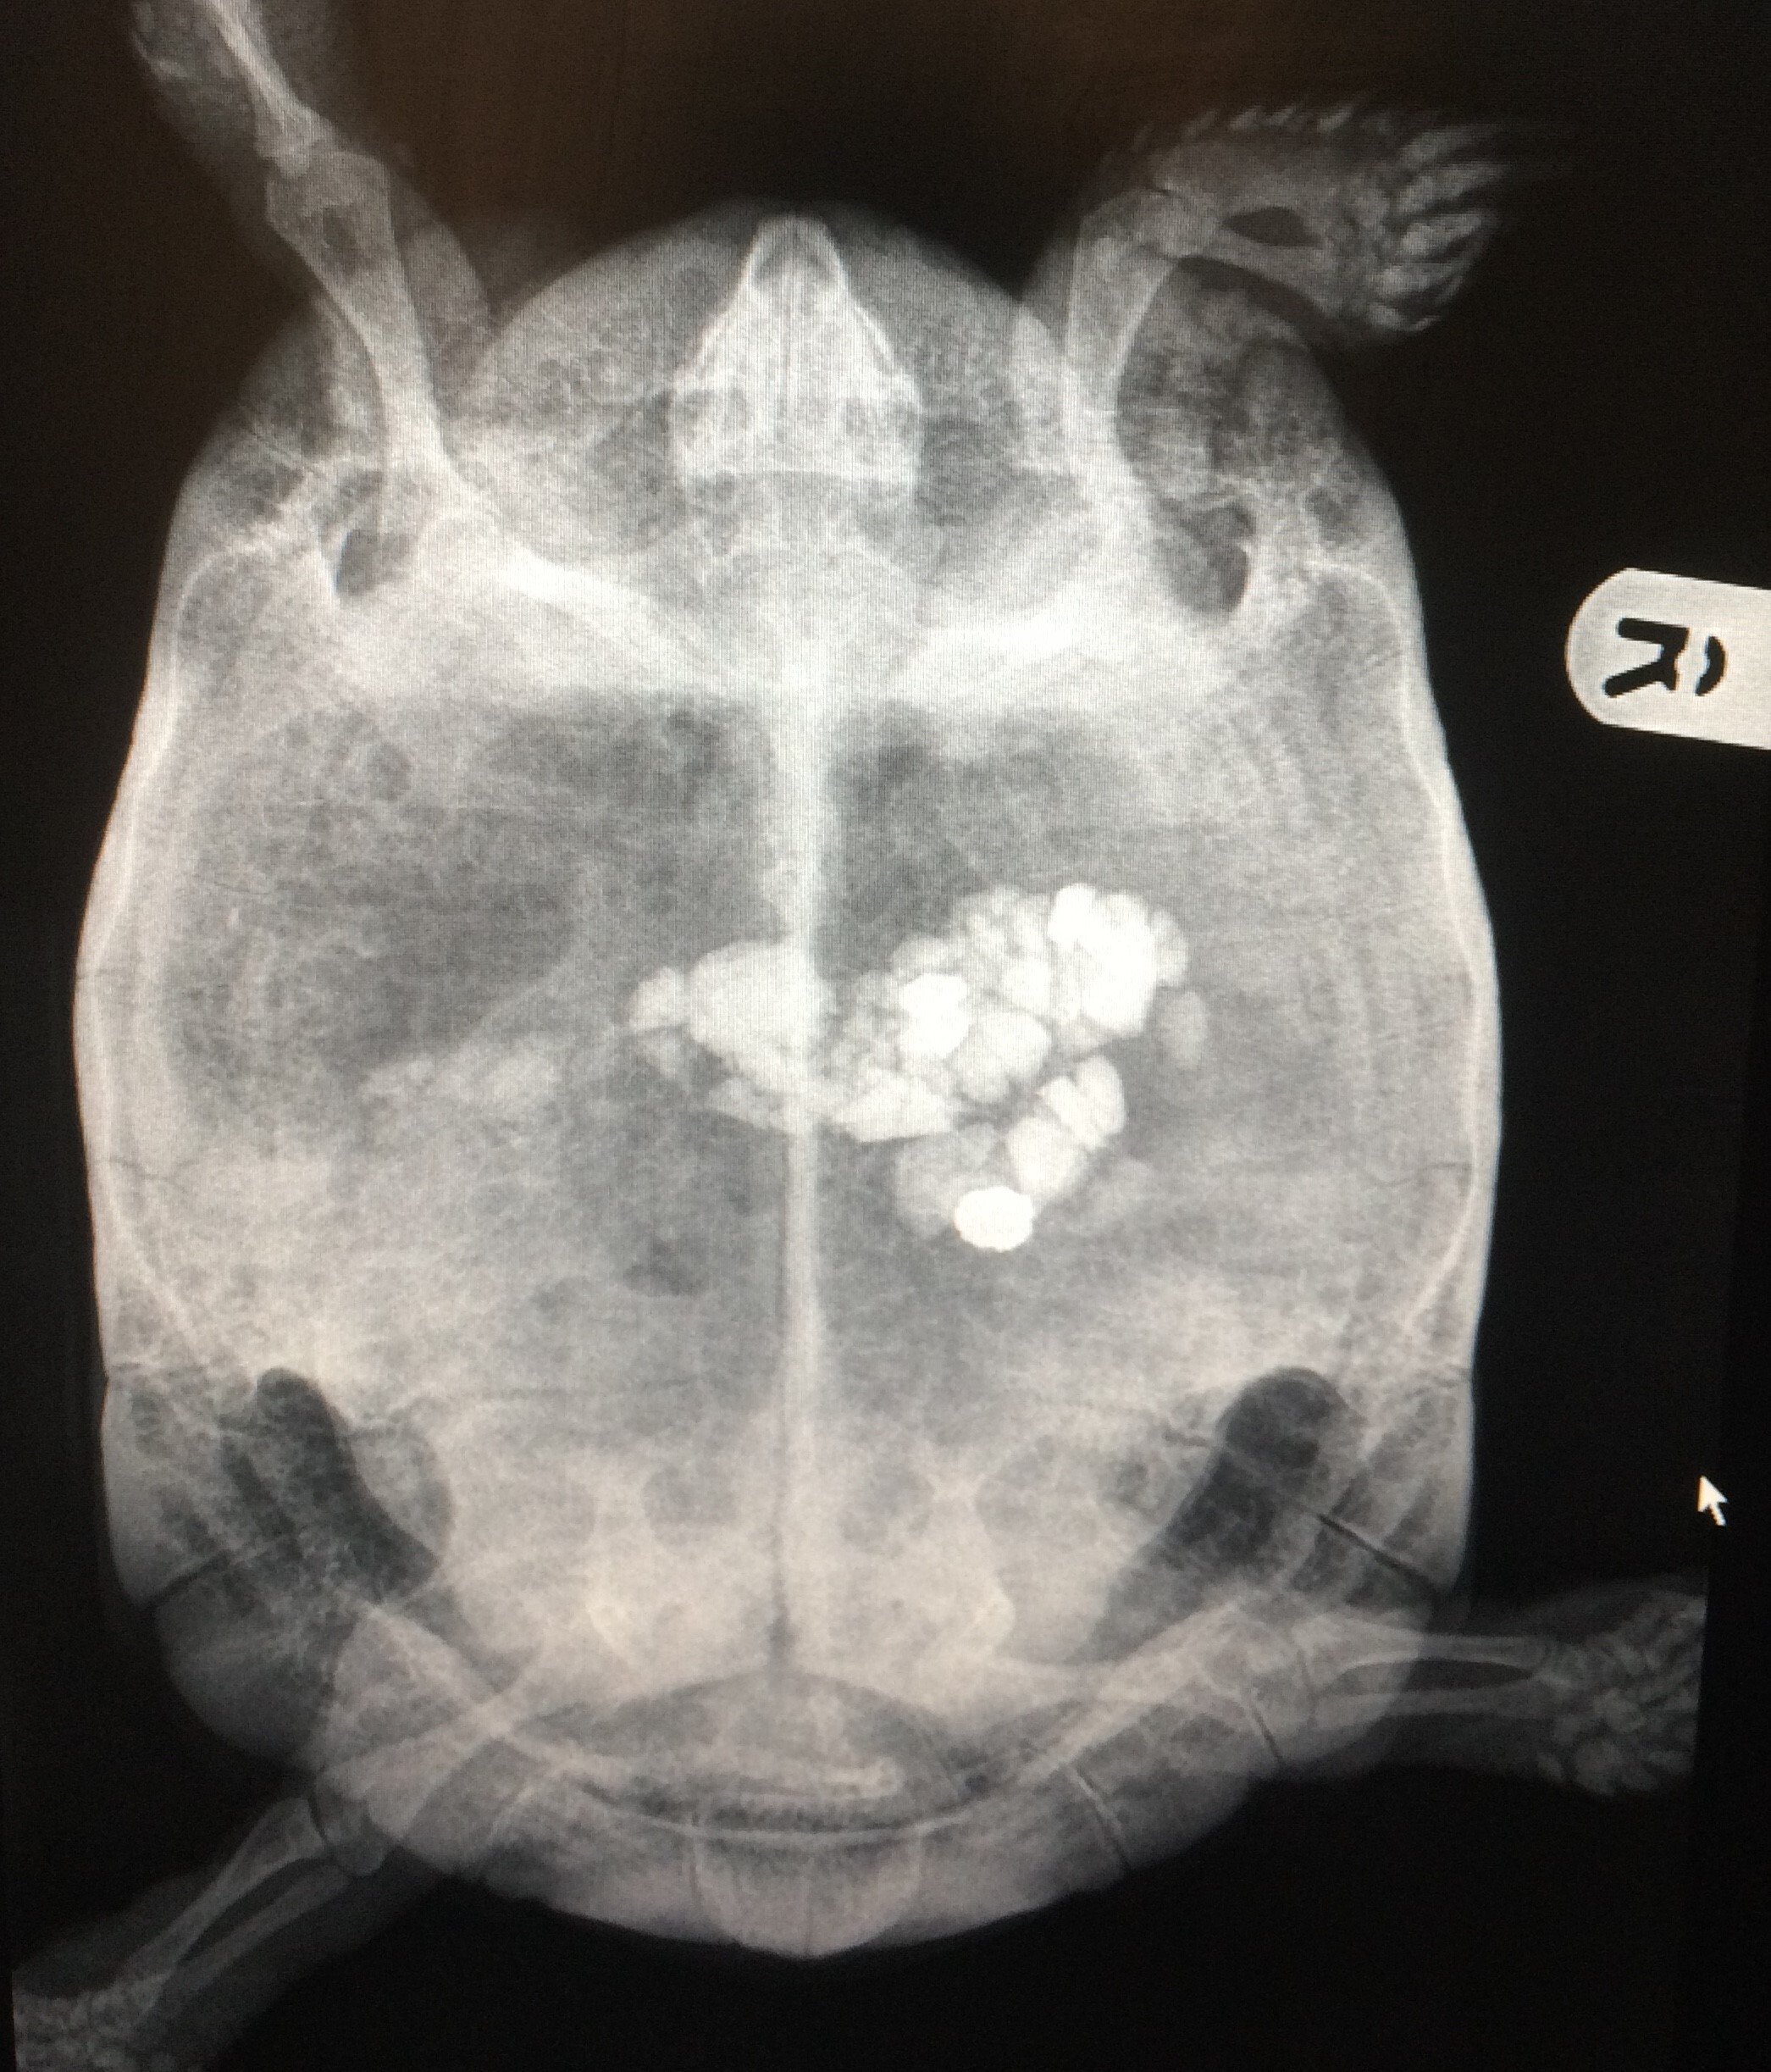

If replacement of the prolapsed tissue is not possible at first presentation, the use of protective wraps such as cling film or plastic wrap can help keep hypertonic saline soaked swabs or lubricant in place, preventing trauma to the prolapsed tissue (McArthur and Machin, 2019a). Initial work-up should always include imaging (McArthur and Machin, 2019a). Radiographs can help identify metabolic bone disease, urolithiasis, presence of eggs (Figure 4) and severe constipation (Figure 5). Other diagnostics to consider include faecal parasitology, biochemistry and haematology, and ultrasound examination (McArthur and Machin, 2019b).